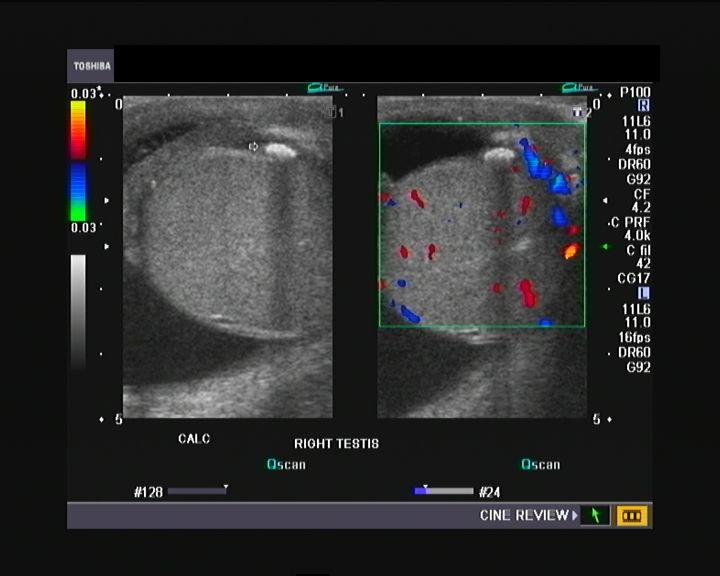

Testiular Pearls

testicular calcification

40% have neoplasm asscoiation

Microlithiasis